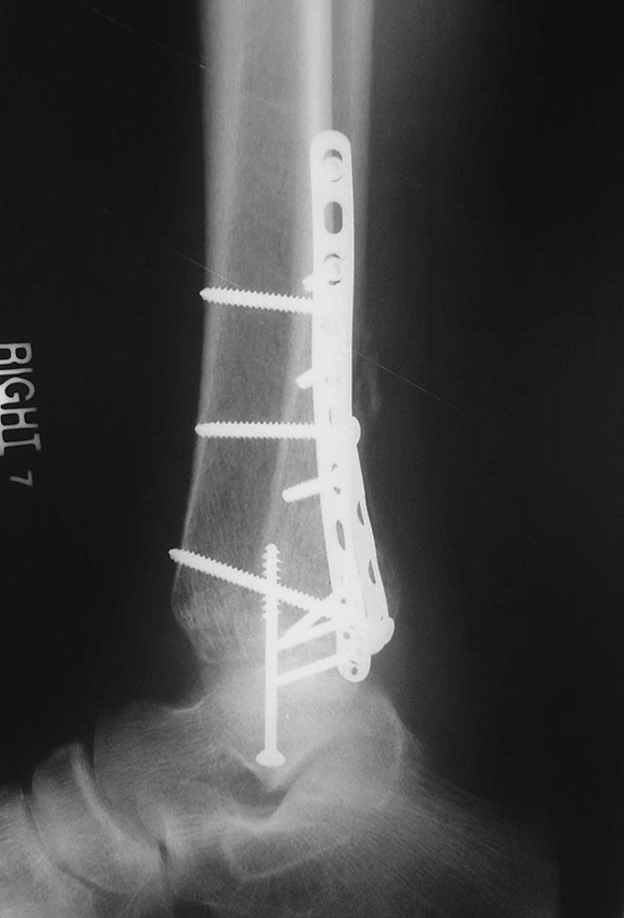

Отправитель: Djoldas Kuldjanov, M.D. 16 Сентябрь 2004, 22:00

Второй случай сделан из одного разреза

Дж

ЕЧ LISS plate, mininvasive approach - luxurous !

На прямой проекции послеоперационного Рг макроскопически все выглядит очень анатомично, при микроскопическом ( :-)) ) рассмотрении можно все-таки заметить вальгизацию тарана, суставная щель в латеральном отделе сустава несколько уже , чем в медиальном при отсутствии латерального смещения тарана. У меня был аналогичный случай (без LISS , без мини доступа) с вальгусным наклоном тарана при восстановленном ankle mortise при последовательном наблюдении с интервалами в 6-8 недель в послеоперационном периоде отмечалось прогрессирующее сужение суставной щели в латеральном отделе сустава, закончившееся посттравматическим ОА, к счастью боли умеренные, купируемые аналгетиками или своими эндорфинами:-))(активная пациентка, у которой нет времени на болезни....) Какова жизненная ситуация в приведенном вами случае? И последнее, что я хотел бы прояснить для себя - фиксация внутренней лодыжки: я обычно комбинирую фиксацию компрессирующим винтом со спицей - по идее ротационная стабильность должна быть лучше, чем один винт, каковы ваши наблюдения в этом плане?